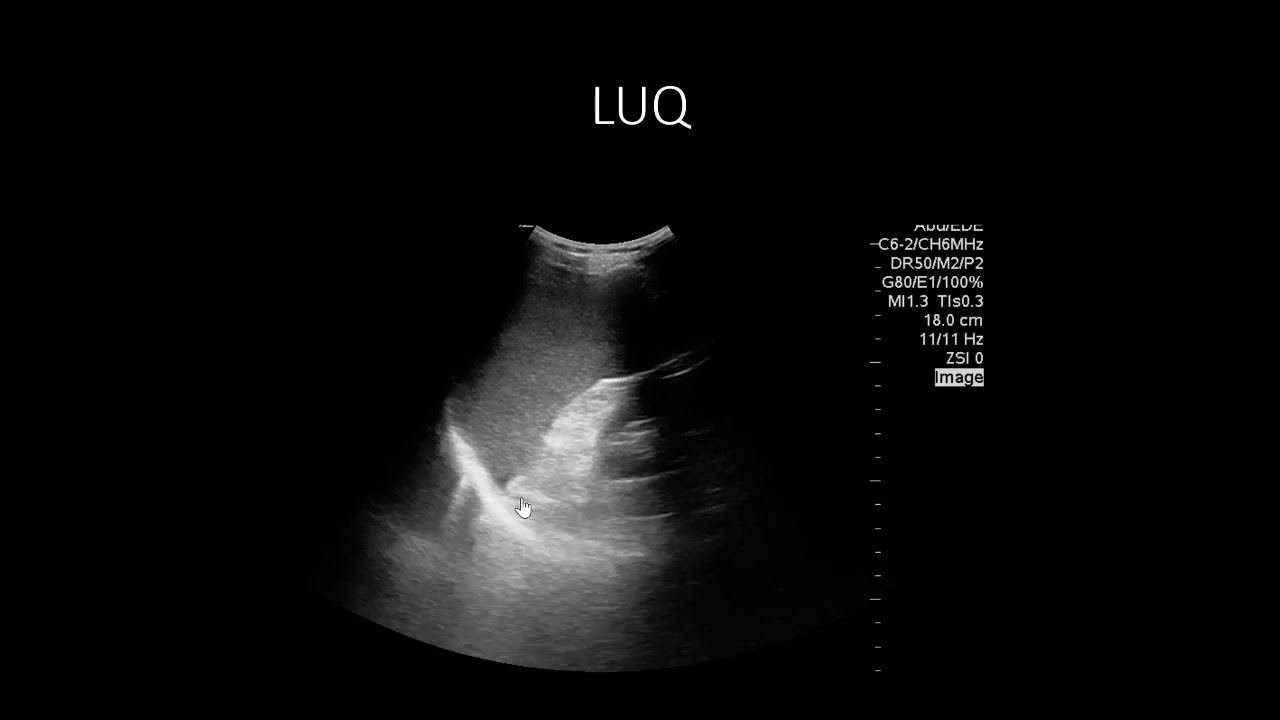

POCUS Cases 9: Abdominal Free Fluid

Описание: Dr. Rob Simard guides us through the abdominal POCUS assessment of the trauma patient on this EM Cases POCUS Cases.